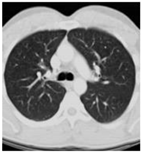

| Types | Original Image | Embedded Image | Noise Image | Output |

|---|---|---|---|---|

| CT | ![]() | ![]() | ![]() | ![]() |